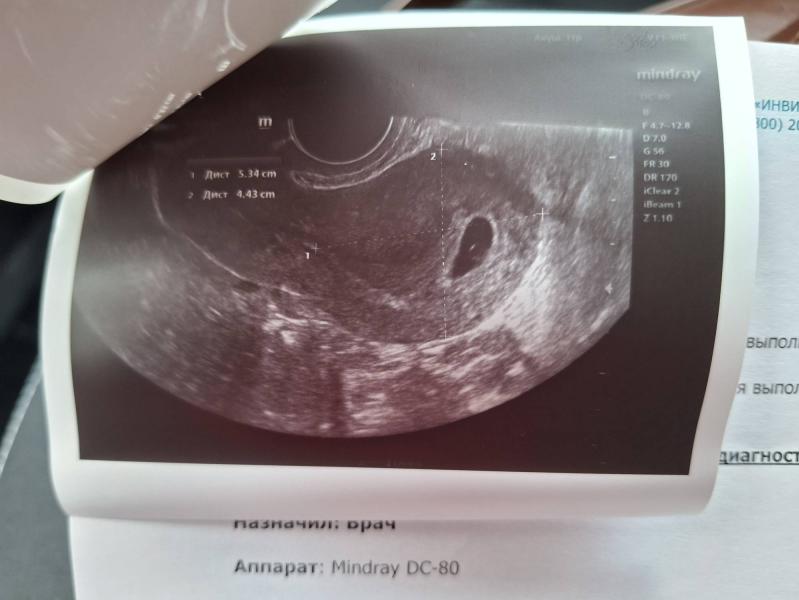

Сегодня было наше первое УЗИ. На недельку меньше малыш, чем по календарю должен.

Посоветовали пересдать ХГЧ в динамике и прийти на повторное УЗИ. И записали к гинекологу в конце октября.

УЗИстка тоже предположила, что овуляция была поздняя. Но я грешу на то, что переболела орви на 4-й неделе, скорее всего поэтому мог замедлиться рост 🥲

Ладно, сдам хгч в динамике, там ясно будет

У меня до 10 недель было отставание в 2 недели) обычная практика .